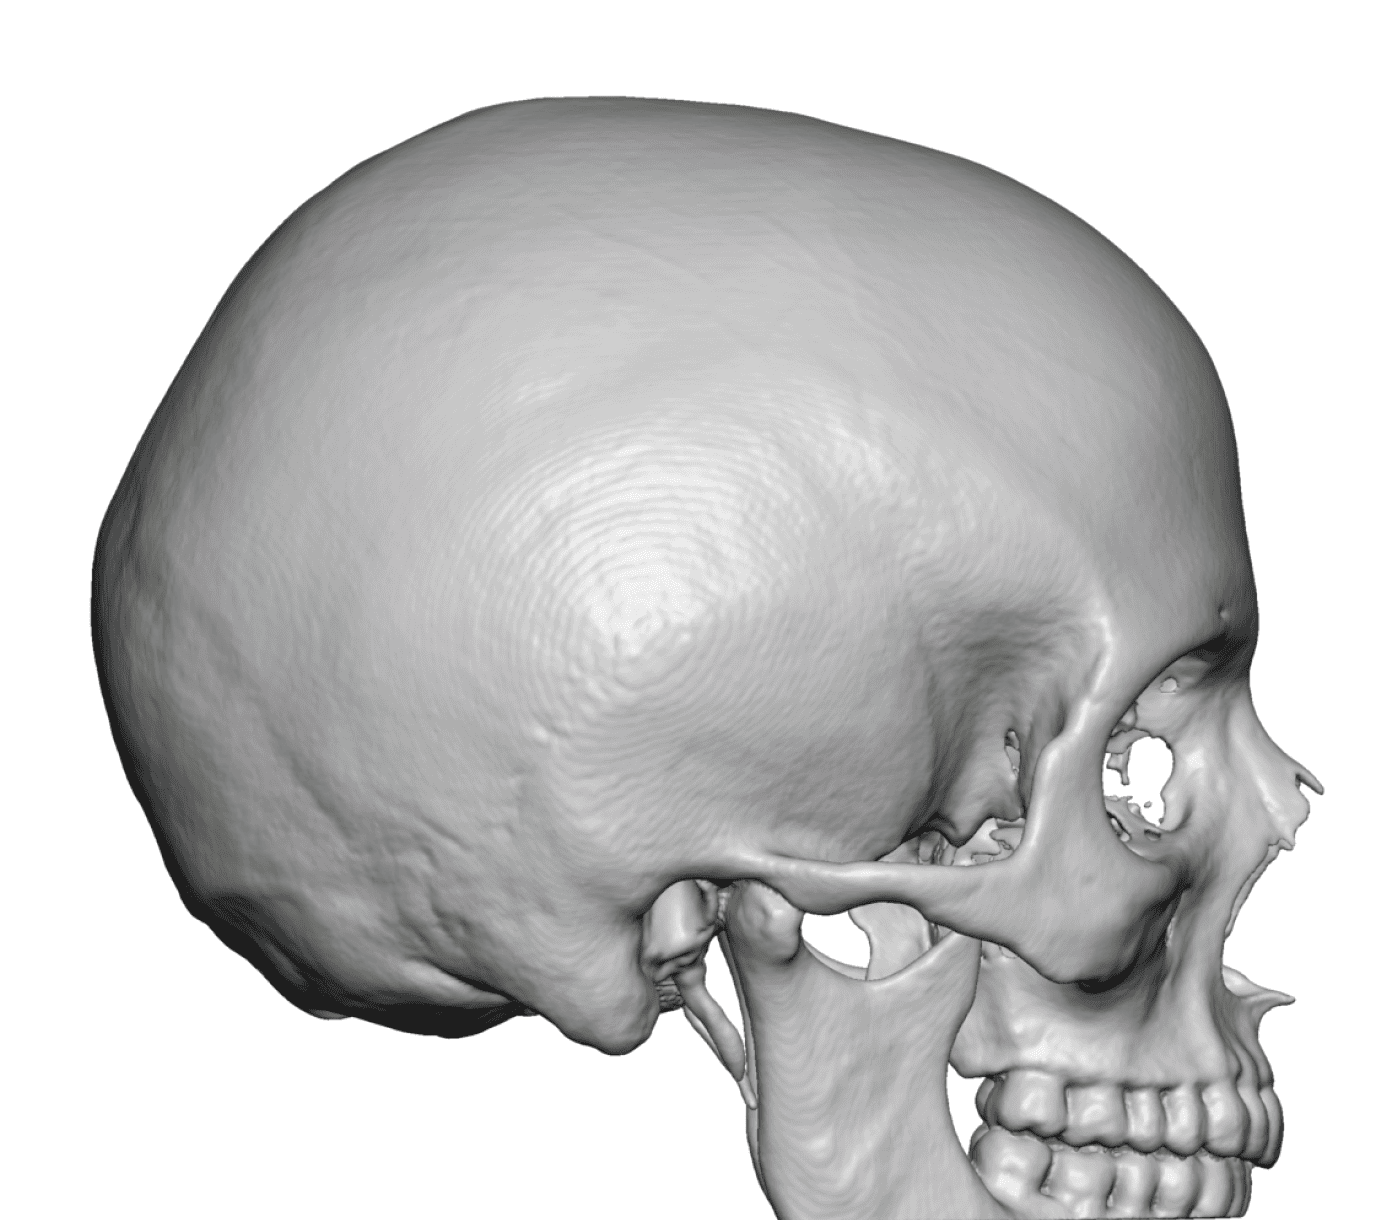

Placement of custom extended forehead-temporal implants through incisions in the crease behind the ear. (he had a prior back of head skull implant which is green in the implant designs and which the head widening implants partially covered it)

Desire for change of head shape from front view form an inverted V shape to a rounder and wider head shape.

Placement of custom extended forehead-temporal implants through incisions in the crease behind the ear. (he had a prior back of head skull implant which is green in the implant designs and which the head widening implants partially covered it)